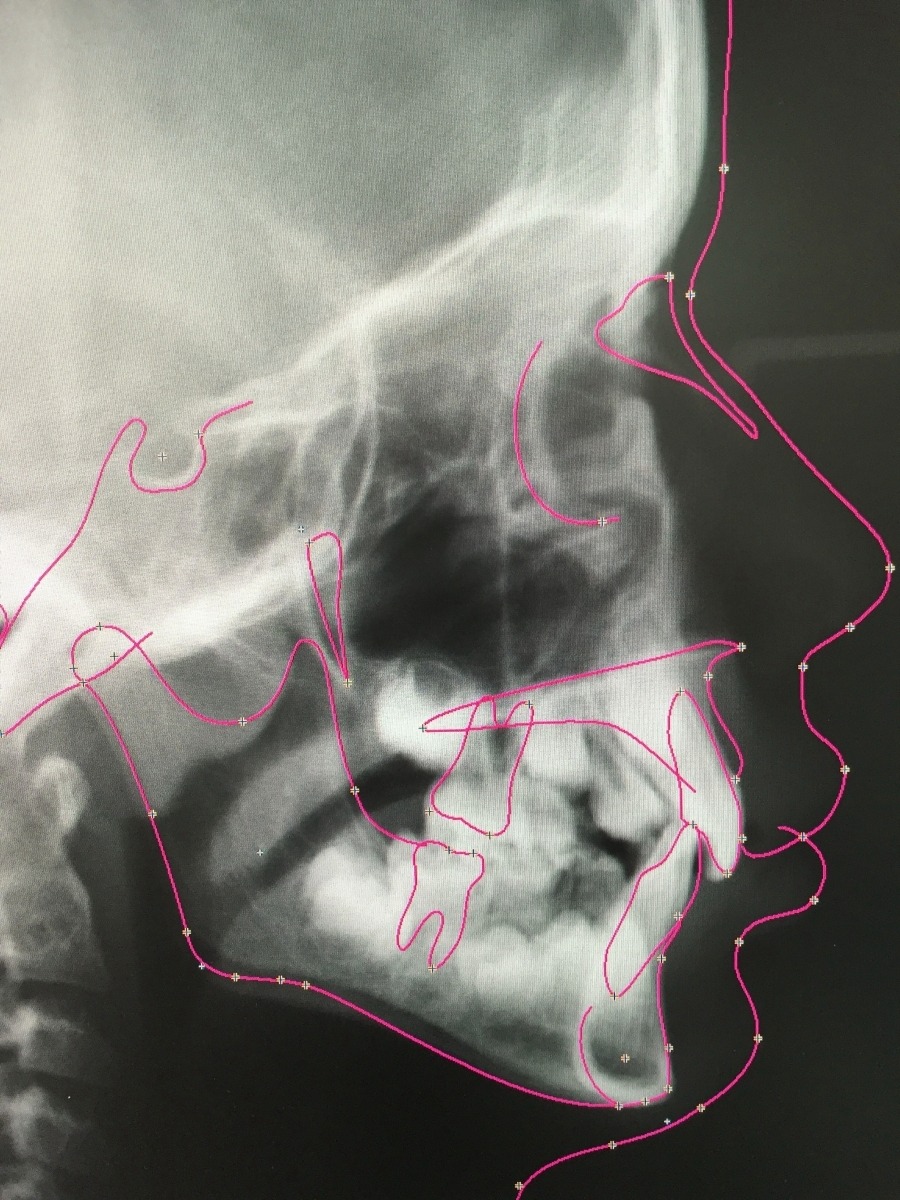

Digitale Kieferorthopädie

Die Diagnostik und Behandlungsplanung erfolgt bei uns vollständig digitalisiert. Dabei spricht man von "digitaler Kieferorthopädie". Dies ermöglicht eine präzise Diagnose, welche den Grundpfeiler für eine individuell auf den Patienten zugeschnittene Therapieplanung bildet. Wir nutzen beispielsweise eine strahlenarme digitale Röntgentechnik, mit der wir die Strahlenbelastung für unsere Patienten auf ein Minimum reduzieren und hochauflösende Bilder mit maximalem Detailgrad erhalten.